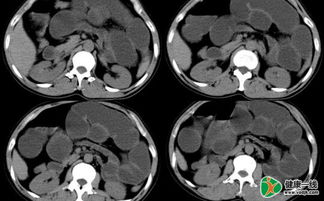

(2) X線檢查:一般梗阻發(fā)生4?6小時(shí)后,立位或側(cè)臥位腹部透視或攝片檢查可見(jiàn)脹 氣腸袢及多個(gè)液平面??漳c脹氣可呈“魚(yú)骨刺”狀;回腸脹氣可見(jiàn)階梯狀液平面;結(jié)腸脹氣 腹部周邊顯示結(jié)腸袋形。

鋇劑灌腸可用于疑有結(jié)腸梗阻的患者,可顯示梗阻的部位和性 質(zhì)。小腸梗阻時(shí)忌用胃腸造影檢查。